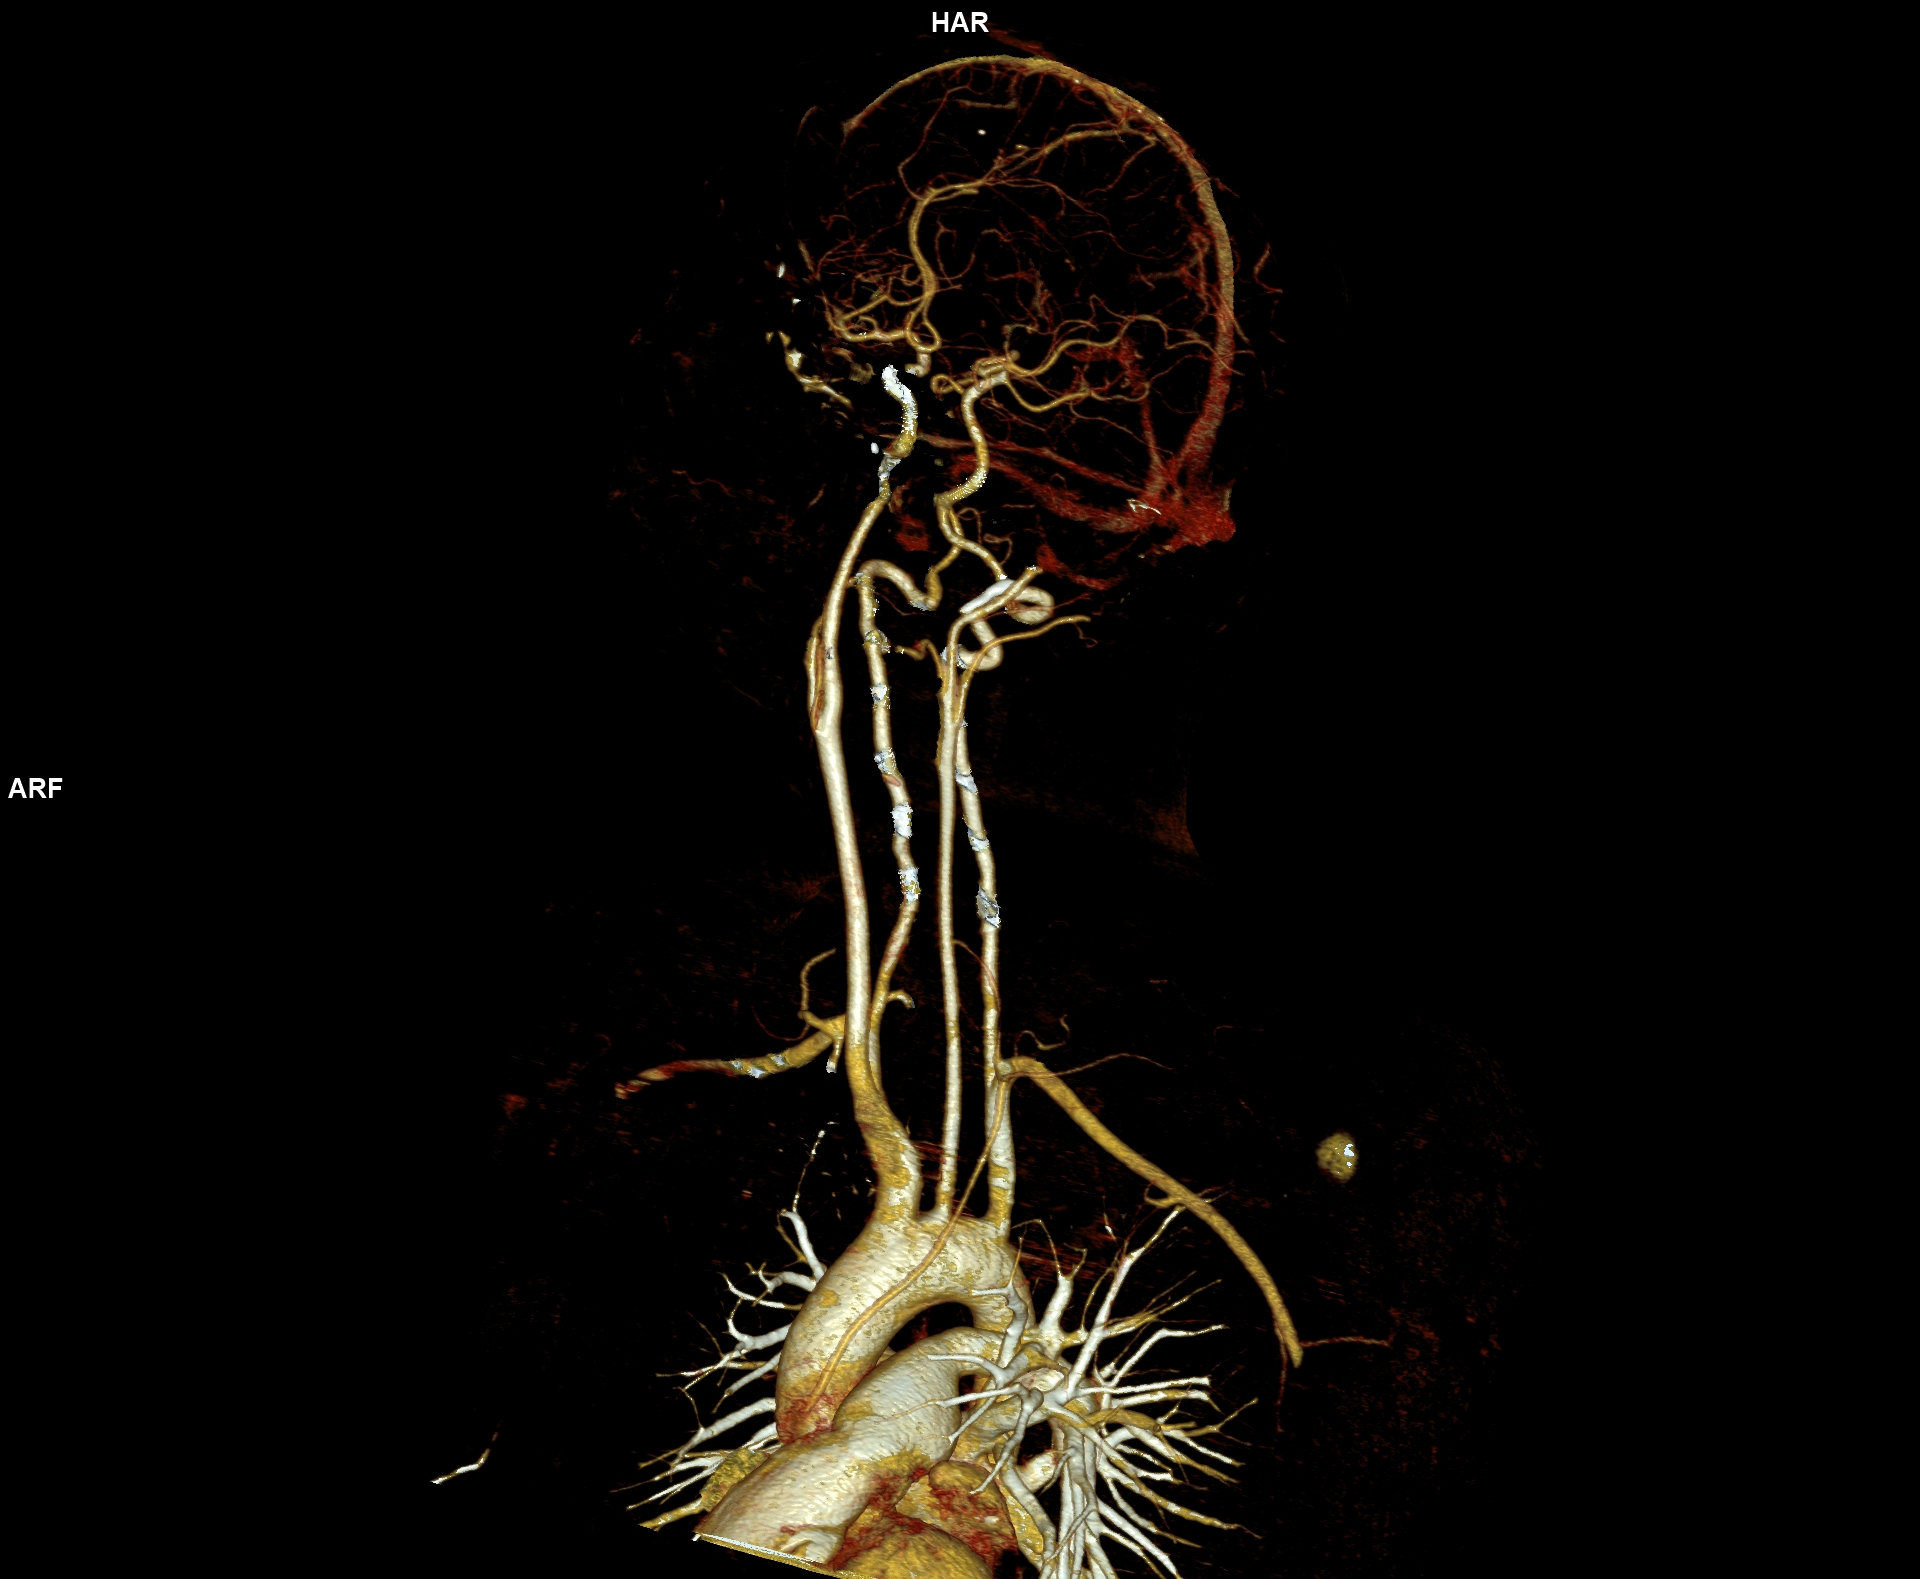

Figura 1, 2 si 3: reconstrucţii VRT din achiziţie angioCT trunchiuri supraaortice

Discuţie caz nr 46: Sindromul Alagille (cunoscut și sub numele de displazie arteriohepatică) este o afecțiune genetică multisistem congenitală sau dobândită cu modificări diverse: hepatice, renale, oculare, otice, scheletale, faciale şi cardio-vasculare. Manifestările cardio-vasculare sunt coarctaţia de aortă şi stenoze vasculare.

Este cazul unei paciente de 24 de ani cu un părinte cunoscut cu Sd Alagille care se prezinta la camera de gardă pentru cefalalgii importante. Examinarea angioCT a evidentiat ocluzie de artera carotidă internă stângă la origine şi a fost completată cu examinare IRM pentru diagnostic diferențial cu disecție de perete vascular.